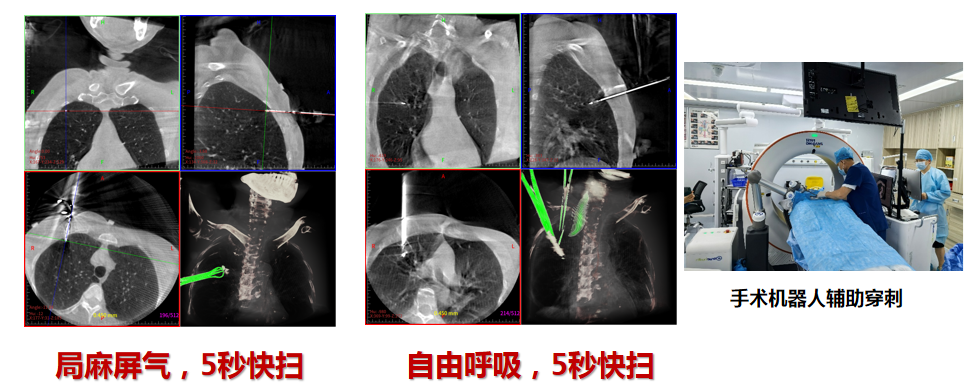

CT扫描与机器人路径规划

穿刺与调针

1. **无需转移CT室**:一体化诊疗平台在手术室内完成全部操作,避免患者转运风险,缩短术前准备时间。

2. **亚毫米级精准**:机器人机械臂基于三维图像实时规划路径,误差小于1毫米,成功命中5毫米微小结节。

3. **大孔径设计**:患者舒适度高,术者操作空间充裕,配合增强透视功能,清晰显示血管与病灶关系。

- **智能算法导航**:机器人自动校正呼吸位移,动态跟踪结节位置,确保消融范围全覆盖。